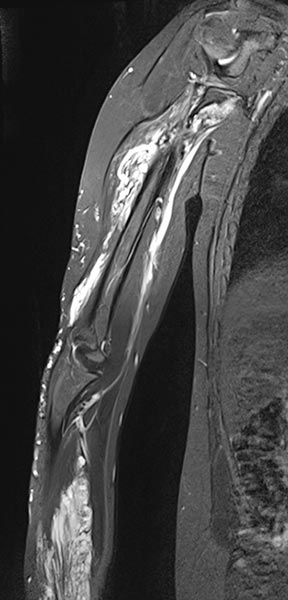

Die koronare, T2-gewichtete, fettunterdrückte Sequenz einer MRT mit Darstellung des rechten Ober- und Unterarms zeigt eine doch deutlich größere Ausdehnung der Malformation als rein klinisch vermutet.

Die Ausdehnung ist vorwiegend subfaszial in der Tiefe der Muskulatur des Ober- und Unterarms. Die Signalgebung ist stark hyperintens, somit sicher eine Slow-flow-Malformation (venös oder lymphatisch).

Die venöse Malformation zeigt in der T2-gewichteten, fettunterdrückten MRT eine tiefe Ausdehnung im Bereich der tiefen Flexorensehnen der Hand und des Unterarmes.

Am distalen Unterarm rechts im Bereich der hauptsächlichen Ausdehnung der Schwellung zeigt sich das Ausmaß der venösen Malformation vorwiegend im Bereich der Flexoren. Stark hyperintenses MRT-Signal in der T2w-Fettsättigung. Die gesamte beugeseitige Muskulatur ist durchsetzt.